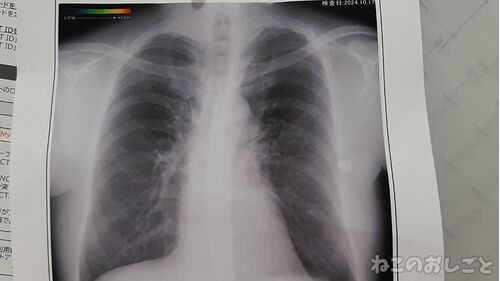

【謎の咳】1ヶ月咳が止まらない! 透明な痰がでる様になったから再び病院へ! 血液検査にレントゲンの結果は・・・

咳がヤバイ! 猫月さん定期的に謎の咳が出るのよ。 大きな病院で色々検査したけど異常無くて 結果逆流性食道炎からの刺激による咳の 可能性がって食道炎のお薬飲んだたら 超治ったの。 それ以来とりあえず他の風邪症状が 無い場合はそのお薬。 とは言え1ヶ月…